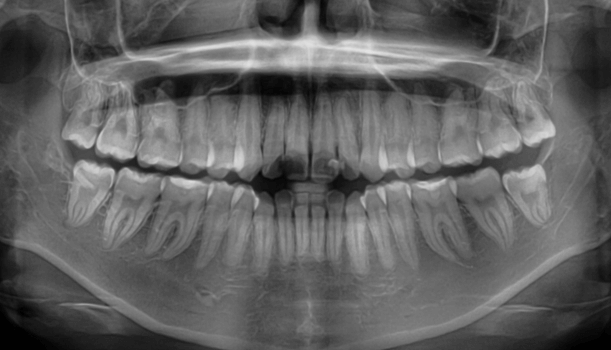

咬み合わせが逆であること(反対咬合)が気になる

| 年齢・性別 | 15歳 女性 |

|---|---|

| 主訴 | 咬み合わせが逆であること(反対咬合)を気にされて来院された女性。見た目や機能面の改善を希望されていました。 |

| 治療期間・回数 | 4年4ヶ月・28回 |

| 費用 | 900,000円 |